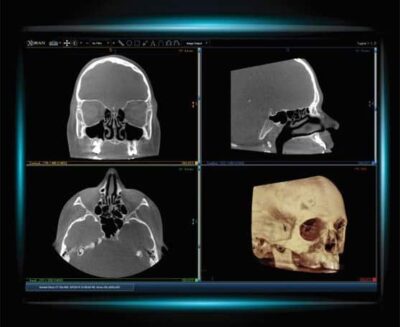

Computed Tomography CT of the Sinuses. Computed tomography of the sinuses uses x-ray equipment to evaluate the sinus cavities. CT scanning is painless, noninvasive and accurate.

Scan times range from 10-30 seconds and include protocols for pediatric patients. A high resolution, digitally versatile CT image is then immediately available on the computer monitor. ​

The scanner creates CT slices as thin as 0.2 mm, with instant views of hundreds of image planes. This isotropic resolution and full range of data provides physicians the information they need to diagnose and treat patients